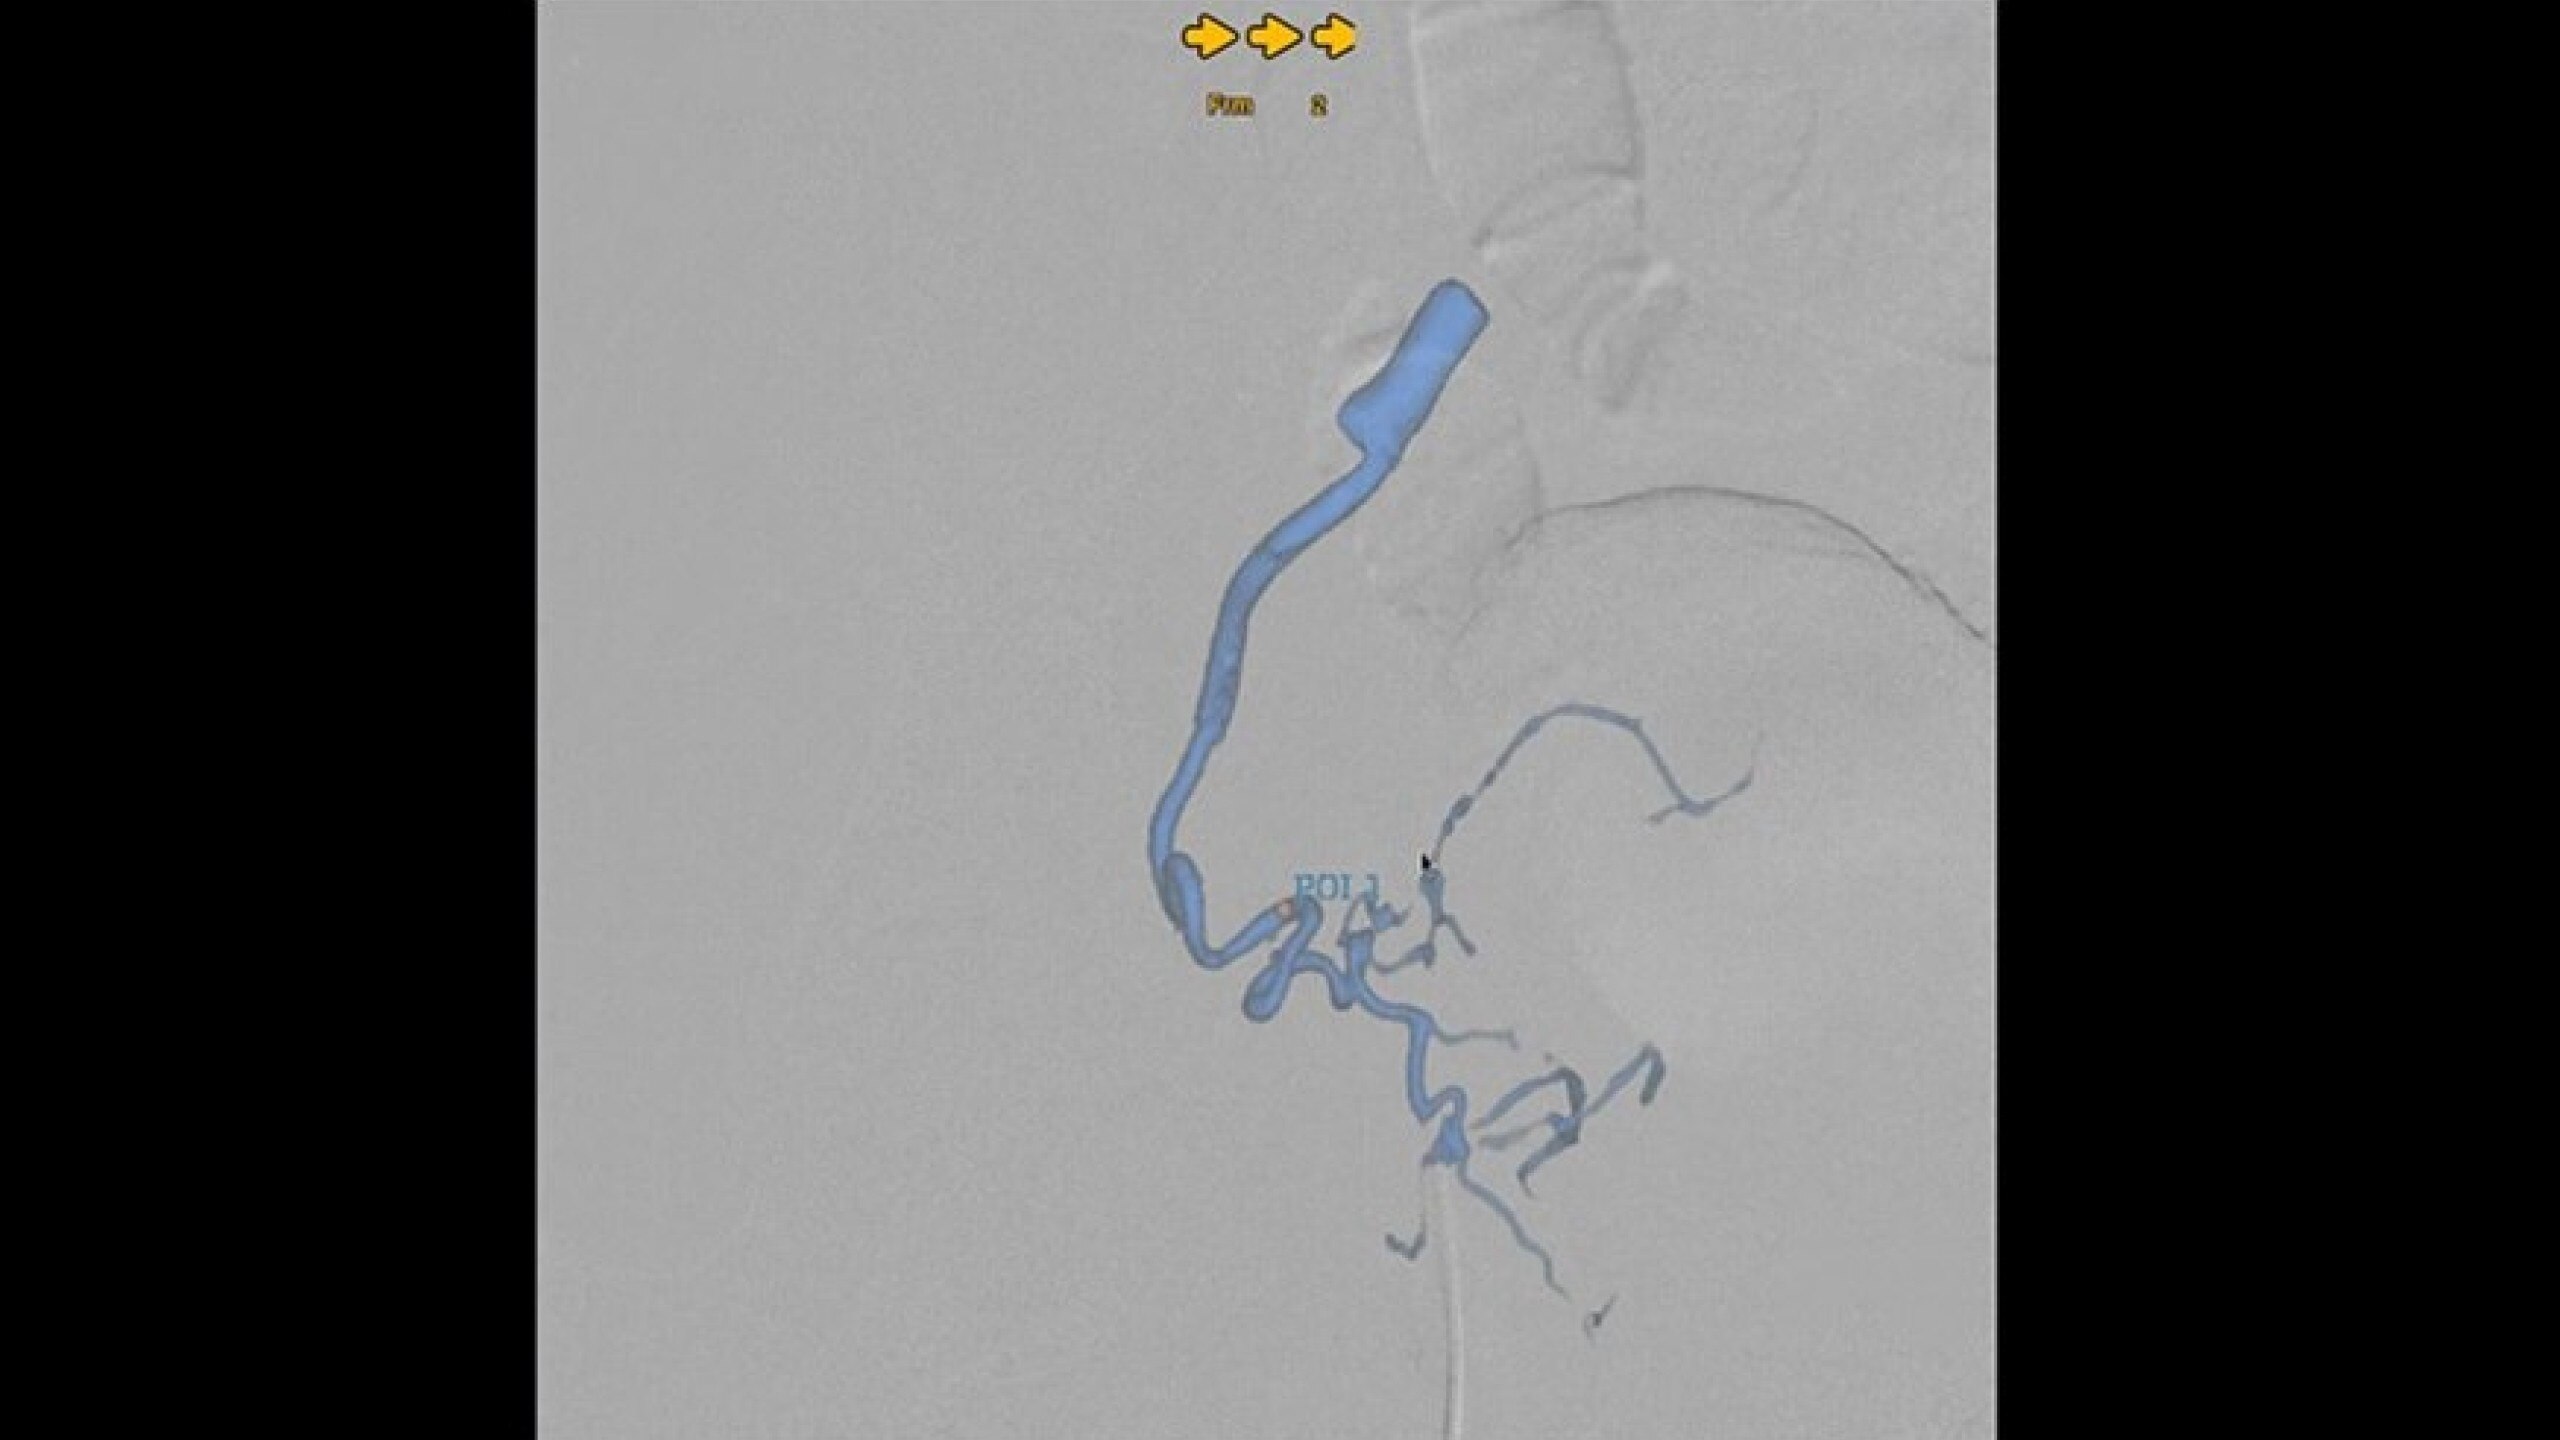

Embo ASSIST is an AI-based augmented guidance solution designed to define optimal embolization strategies and streamline your clinical workflow.

Dynamic simulation at different injection points

Visualize multiple vessels and navigate in cross sections to facilitate planning